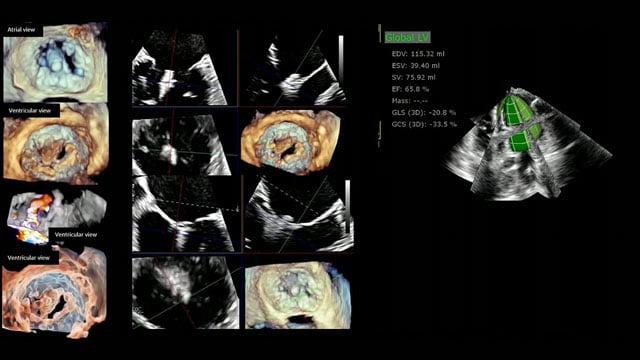

Focused on the often-overlooked right ventricle, this session elucidates methods for accurate assessment of right ventricular function prior to transcatheter tricuspid valve interventions. It explores the role of right heart catheterisation in patient selection and timing, and evaluates long-term remodeling patterns post-procedure, providing critical insights for...